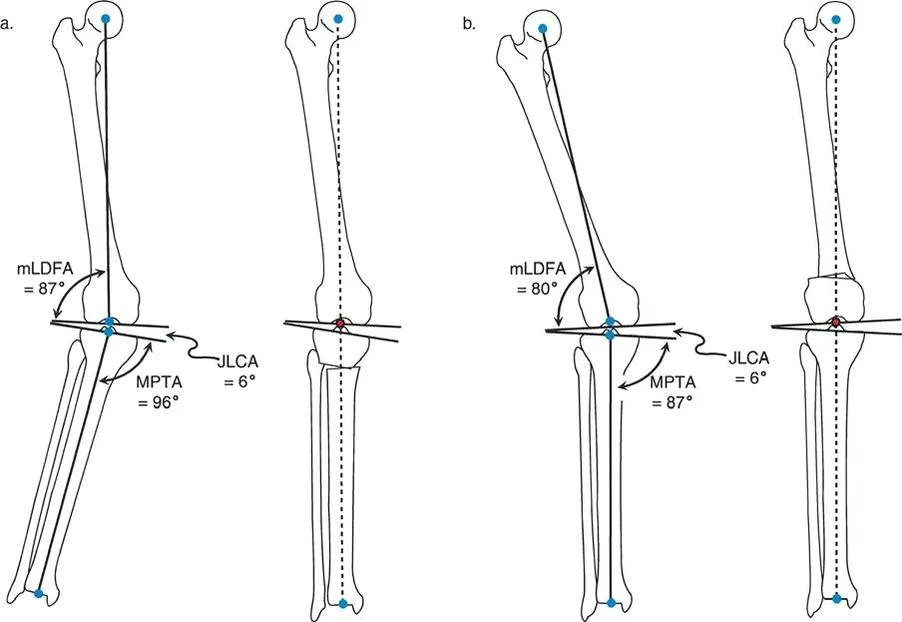

- الأشعة السينية الطويلة للطرف السفلي بالكامل أثناء الوقوف (Standing Long-Leg AP View): تُعد هذه الأشعة حاسمة لتقييم المحاذاة الميكانيكية للطرف السفلي بأكمله. تُظهر بدقة درجة الانحراف الأفحج (Varus) أو الأروح (Valgus) وتساعد في تحديد مركز دوران التشوه (CORA).

غالبًا ما ترتبط خشونة الركبة الإنسية بالانحراف الأفحج (Genu Varum). يهدف العلاج إلى تحويل الحمل من الحجرة الإنسية المتضررة إلى الحجرة الوحشية السليمة.

علاج خشونة المفصل أحادي الحجرة الوحشية (LCOA)

ترتبط خشونة الركبة الوحشية غالبًا بالانحراف الأروح (Genu Valgum). يهدف العلاج إلى تحويل الحمل من الحجرة الوحشية المتضررة إلى الحجرة الإنسية السليمة.

- ملاحظة هامة: يجب تصحيح LCOA إلى محاذاة محايدة (MAD = 0 مم) فقط، على عكس MCOA التي غالبًا ما يتم تصحيحها بشكل مفرط قليلاً إلى وضعية الأروح. هذا لتجنب تحميل زائد على الحجرة الإنسية.